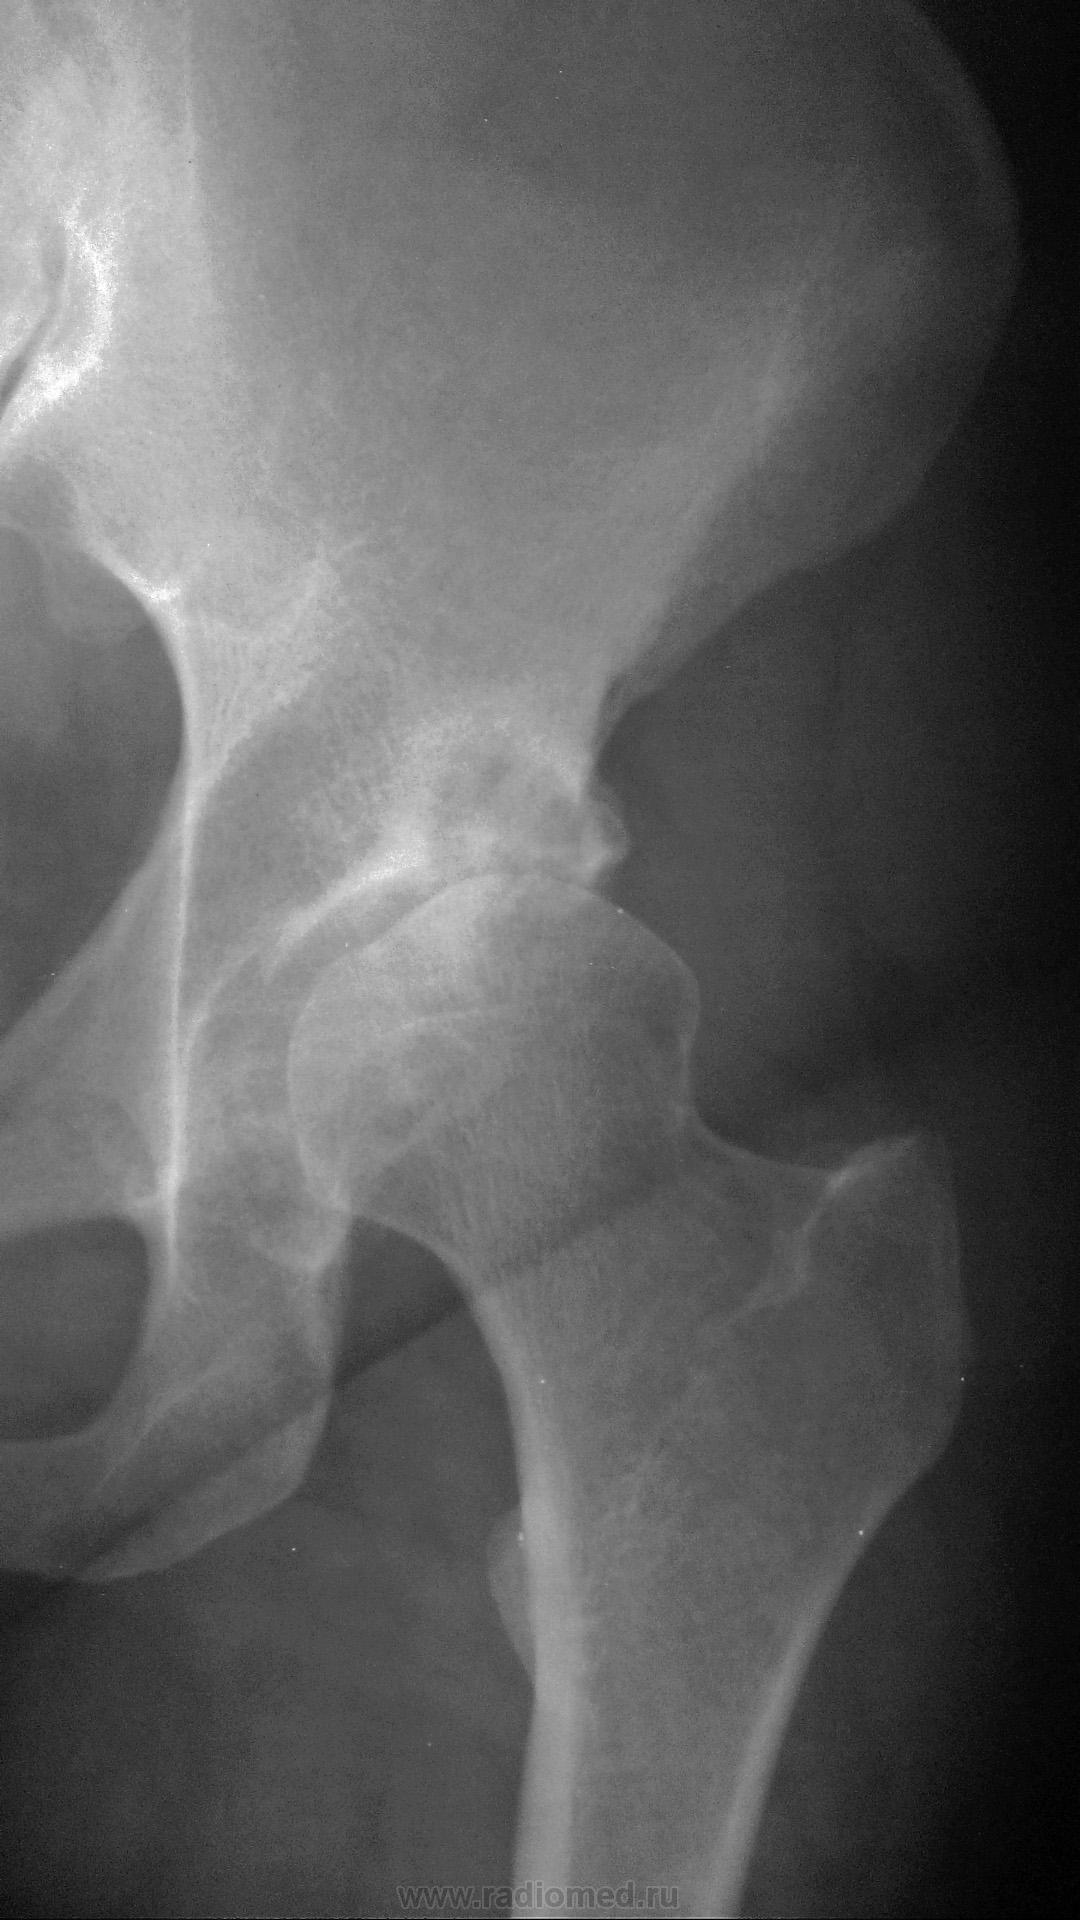

Отлично, Медея! Сумела улучшить денатурированную репродукцию снимка, а до того увидеть суть проблемы. Вот что значит объёмное восприятие объекта, свойственное Настоящему Рентгенологу. Да, здесь множественные разнокалиберные кисты почти по всему периметру впадины, а в обл. крыши одна близка к прорыву в полость сустава. В этом случае томография для уточнения стадии необходима.

Кистовидная перестройка вертлужной впадина имеется, безусловно. Первичная или вторичная? Но имеется кистовидное просветление, которое относится к головке, а не к впадине. И сколько не абстрагируйся от суперпозиции головки и впадины, без второй проекции структуру головки не выяснить.

Похожий случай, только ещё головка задействована